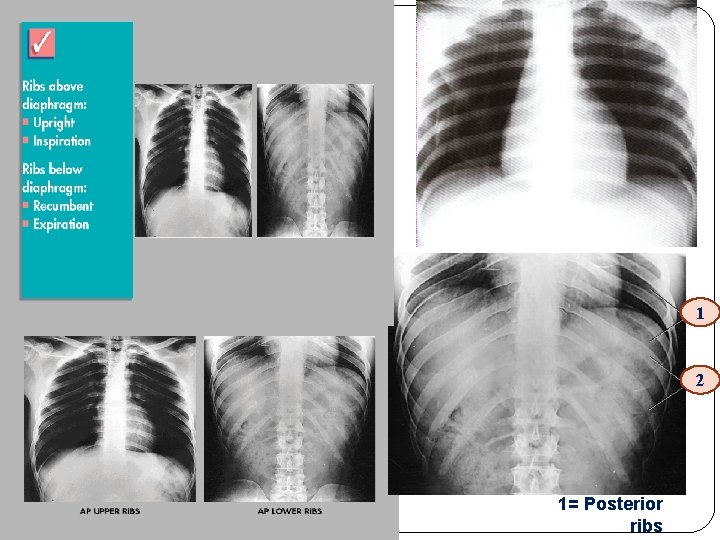

SS above diaphragm : ribs 1 – 9 or 1 10 should be seen below diaphragm ribs 8 - 12 should be seen.

1 2 1= Posterior ribs